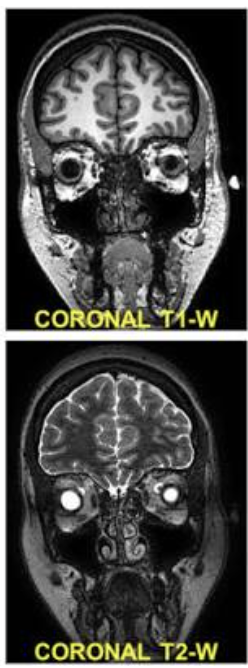

What is MRI?

A cross-sectional imaging technique using a magnetic field and radiofrequency signals to generate images from hydrogen nuclei in water molecules

How are coronal MRI images viewed?

From the front facing the patient

How are sagittal MRI images viewed?

From one side of the body to the other

How are axial MRI images viewed?

From the feet toward the head like CT

What are the three basic components of MRI?

Scanner

Operator console

Computer

How does MRI work in basic terms?

Scanner creates a small magnetic field

Hydrogen protons in water molecules in tissues align with a magnetic field

Then a radiofrequency pulse disrupts them, then released energy is converted into an image

Why do different soft tissues look different on MRI?

Different tissues have different water content and release absorbed energy at different rates

What determines the construct of an MRI image?

The sequence used

What are the two common MRI sequences?

T1-weighted and T2-weighted

What is a basic tenet of MRI?

Define anatomy (T1)

Detect abnormal fluid (T2)

Hint: H2O → T2

White = edema in photo

How does pathology often appear on MRI?

Pathology commonly involves edema or inflammation

What does high signal intensity mean on MRI?

Brighter image

What does low signal intensity mean on MRI?

Darker image

How does water or edema usually appear on T2-weighted MRI?

Bright

What are common clinical indications for MRI?

Soft tissue injuries

Bone marrow changes

Intervertebral disc pathology

What is a limitation or disadvantages or contrindications of MRI for bone?

Cortical bone is not well seen because of low signal intensity

Longer time

Claustrophobia

High cost

Metal implant contraindications